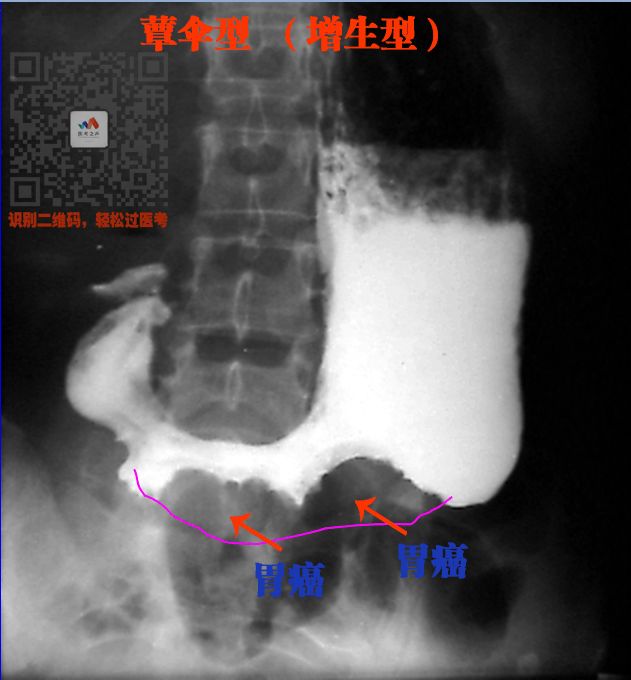

④ 胃癌

胃癌有不同的生长方式

所以表现也不一致

增生型

胃腔里面突出一个肿瘤

这块肿瘤不能被钡剂填充

所以表现充盈缺损(胃好像掉了一块)

浸润型

肿瘤沿着胃壁生长

把胃壁搞得失去弹性

变得很窄,所以只能看到一点钡剂

看图

胃部就考两2个病:

墙(轮廓)内犯人(坏),墙外好人

向轮廓外突出一个小鸡鸡,选胃溃疡

胃里面钡剂少了(充盈缺损,狭窄)

就选胃癌